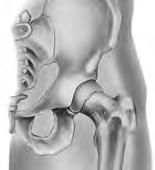

El reemplazo total de cadera (artroplastia de cadera) es una operación para reemplazar una articulación de la cadera dañada por desgaste, lesión o enfermedad. La articulación de la cadera es una articulación de "rótula y encaje" y es la articulación que soporta peso más grande. La parte superior esférica del fémur (hueso del muslo) se posa sobre la cavidad acetabular (área hueca) del hueso pélvico. La articulación se mantiene unida mediante ligamentos y músculos. La cavidad está recubierta con cartílago (tejido firme y flexible) que se puede dañar o desgastar, y causar dolor. La artritis, las infecciones, las lesiones o la pérdida de flujo sanguíneo en la cavidad del fémur pueden dañar la articulación. Es posible que necesite una cirugía de reemplazo total de cadera si sufre de dolores incesantes o problemas para caminar.

El cirujano hará una incisión (corte) en la cadera. Durante la operación, el cirujano hará a un lado algunos músculos y otras estructuras para tener acceso a la articulación de su cadera. Se quitarán las partes dañadas de la articulación de su cadera mediante el uso de herramientas especiales. Se colocarán implantes metálicos, cerámicos o plásticos para reemplazar la parte de los huesos que fue removida. Luego, el cirujano puede fijar los implantes con tornillos y cemento, o crear un ajuste firme si la calidad del hueso así lo permite. Una vez colocados, se los une como si se metiera una esfera dentro de una cavidad, y se colocan los músculos y tejidos alrededor de la articulación nuevamente en su posición original. La incisión se cerrará con puntos, grapas o pegamento, y se cubrirá con un vendaje. Someterse a esta operación puede aliviar su dolor, mejorar la estabilidad de su cadera y mejorar el movimiento de su pierna.

Componentes del reemplazo de cadera

Cubierta acetabular Pinnacle

Revestimiento de polietileno

Cabeza femoral

Vástago femoral